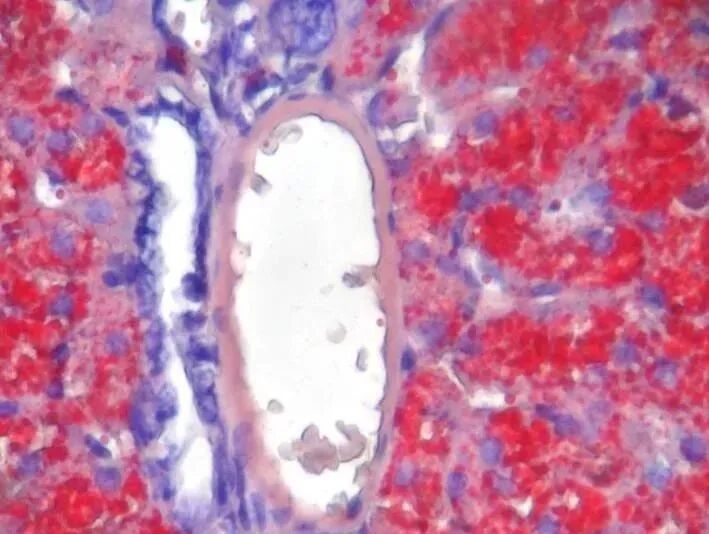

Masson三色染色胃癌组织中血管平滑肌